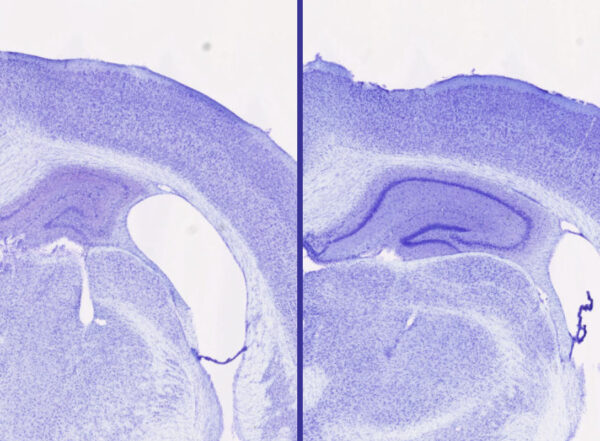

Tag: sleep April 2, 2026 What’s Actually the Best Way to Get a Good Night’s Sleep? We Asked ScientistsSource: Gizmodo January 22, 2026 Breathing disruptions during sleep widespread in newborns with severe spina bifidaStudy reveals gap in screening and treatment that could improve developmental outcomes.News Release January 20, 2026 This Is the Optimal Way to Nap, According to Sleep ExpertsSource: Women's Health December 24, 2025 Stimulant ADHD medications work differently than thoughtBrain areas affected by the drugs control reward and wakefulness, not attention, study shows.News Release December 6, 2025 Sleep banking helps you get some rest in advanceSource: CNN May 27, 2025 Sleep aid blocks neurodegeneration in miceLemborexant, similar sleep drugs show promise in treating disorders related to tau, such as Alzheimer’s disease.News Release February 28, 2024 Neurons help flush waste out of brain during sleepFindings could lead to new approaches for Alzheimer’s, other neurological conditions.News Release October 20, 2021 Hit the sleep ‘sweet spot’ to keep brain sharpToo little and too much sleep linked to cognitive decline.News Release May 8, 2020 Flies sleep when need arises to adapt to new situationsStudy in fruit flies may shed light on sleep as an evolutionary tool.News Release March 26, 2020 Insight into Alzheimer’s early stages provides clues to treatment strategiesTau protein changes years before cognitive symptoms.News Release January 24, 2019 Sleep deprivation accelerates Alzheimer’s brain damageStudy in mice, people explains why poor sleep linked to Alzheimer’s .News Release Posts navigation